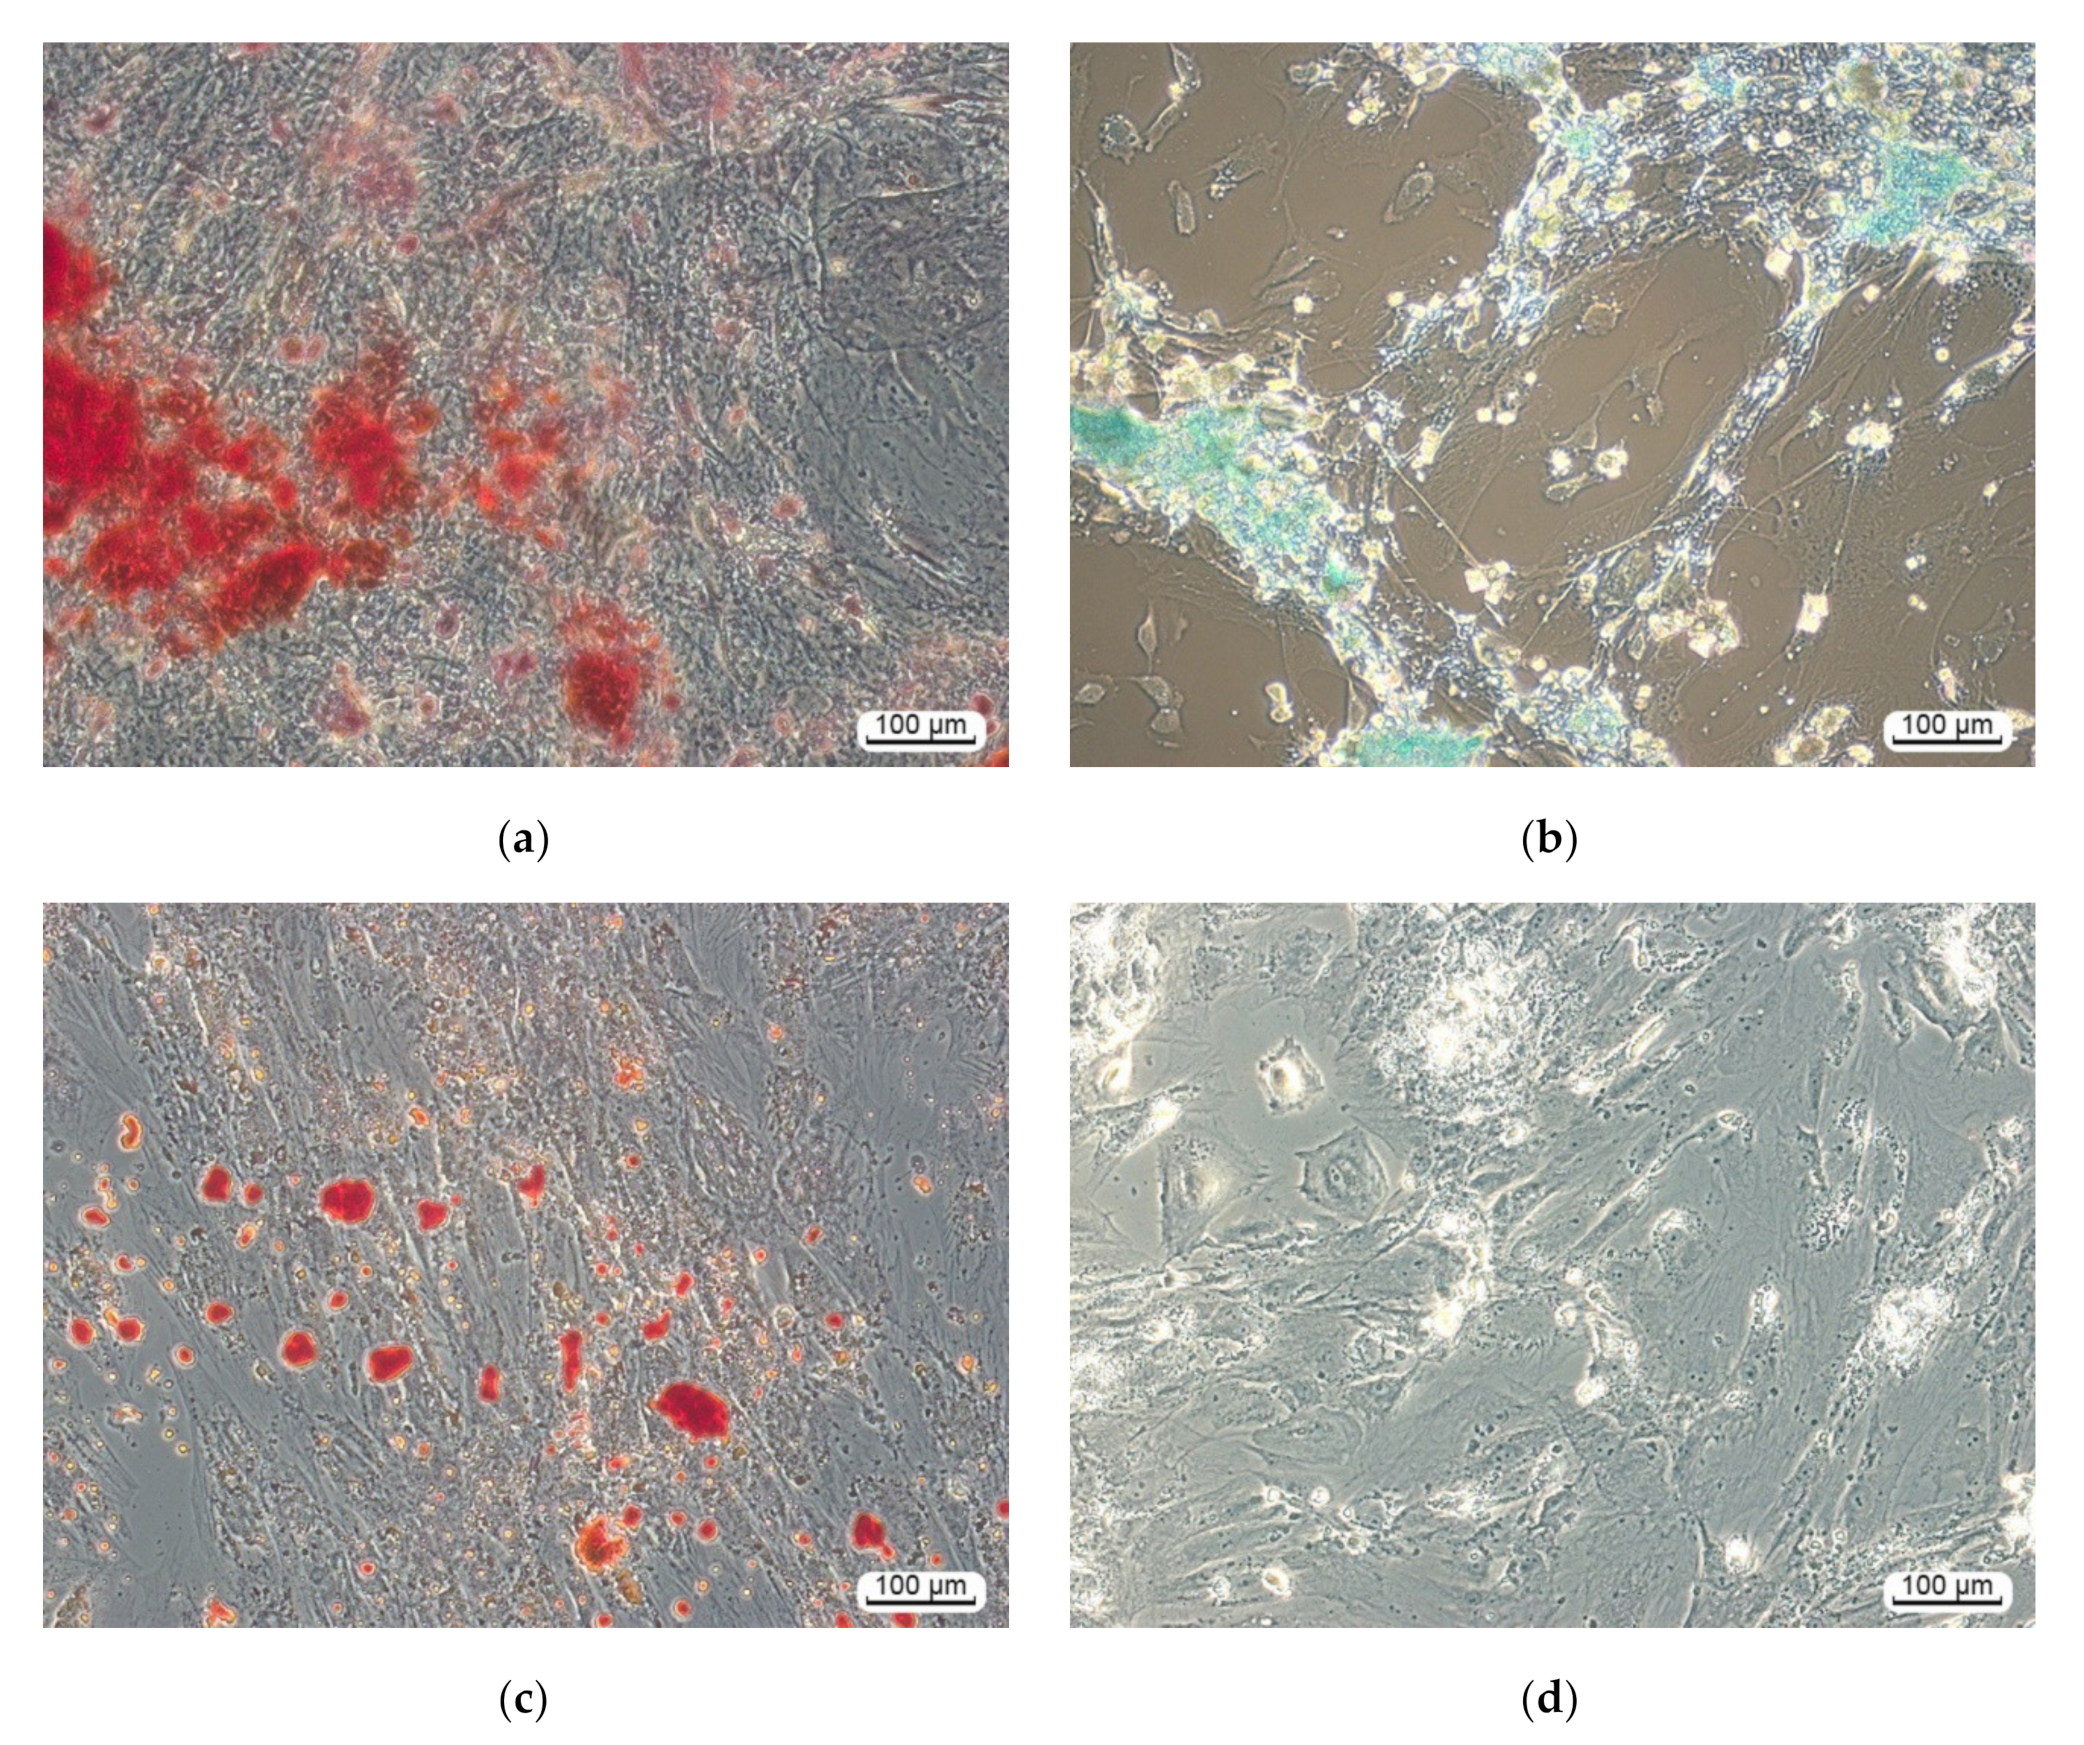

3.2.1. Multilineage Nature of hAMMSC Culture

3.2.2. hAMMSC Morphology and Motility